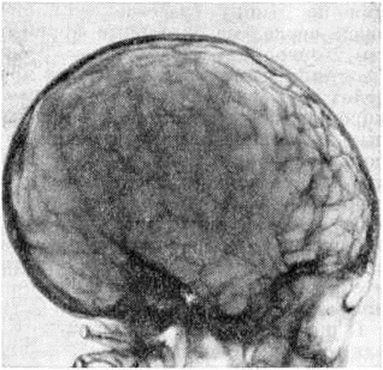

Повышение внутричерепного давления проявляется на краниограммах (рисунок 3) истончением костей свода, усилением рисунка пальцевидных вдавлений (симптом кованого серебра»), углублением борозд синусов, образованием дополнительных венозных выпускников, изменением турецкого седла и расхождением необлитерированных швов.

Рис. 3. | ||